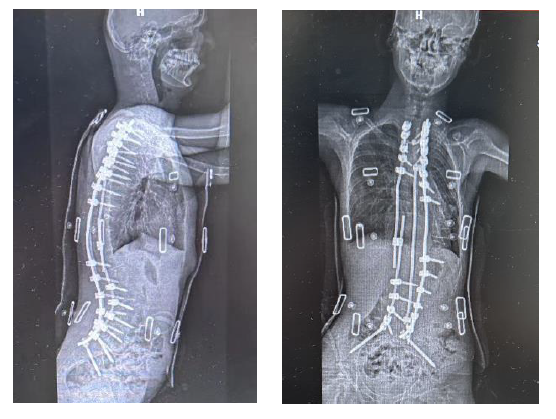

手术前男孩的脊柱。 本文图片均为上海新华医院提供

随后的两年,这名男孩在当地长期行激素治疗、血浆置换等综合治疗,病变没有得到明显控制,反而背部弯曲程度逐渐加重,侧弯角度达162度,后凸109度,明显躯干失衡,呼吸功能障碍等症状。

手术后男孩的脊柱。

在经历了耗时5个月的牵引治疗后,患儿呼吸功能改善,基本达到手术条件。同时脊柱畸形程度减轻,侧弯从原来的162度变为97度。

随着伤口的逐步愈合,目前男孩的住院治疗阶段已经结束,他的站姿、坐姿都获得了明显的改善,术后影像提示侧弯及后凸得到明显纠正,侧弯角度从162度纠正至38度,后凸从109度纠正至36度。同时,随着矫正的成功,他的心肺功能也将逐步得到改善。